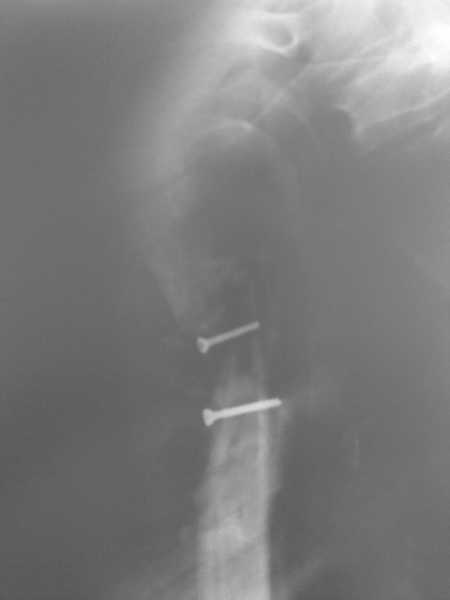

[Ortho] Ложный сустав в/3 плечевой кости!

Здравствуйте, коллеги!!! К нам в отделение госпитализирован пациент 39 лет с

клинико-рентгенологической картиной ложного сустава в/3 плечевой кости! Снимки

прилагаются! Предистория такова: около года назад получил оскольчатый перелом в/3

плечевой кости. В одной из московских больниц выполнен остеосинтез пластиной, через

несколько месяцев выполнен реостеосинтез, опять же пластной...., причины реостеосинтеза

со слов пациента таковы - "доктору не понравилась как лежит пластина и он ее переложил..." -

два месяца назад выполнено удаление фиксатора. Никаких выписок у больного нет. Около недели

обратился в травмопункт, откуда направлен к нам. Клинически у пациента имеется подвижность

в области в\3 плеча, костная крепитация, умеренная болезненность в в/3 плеча при движениях,

атрофия дельтовидной мышцы. На следующей недели планируем пациента опериравать. Коллеги,

у нас возникло несколько вопросов, если не затруднит, то посоветуйте и подскажите... Мы

планируем выполнить закрытый блокируемый остеосинтез, скажите пожалуйста, нужно ли в этом

случае, на ваш взгляд, выполнять костную пластику или достаточно выполнить рассверливание

костномозгового канала и заштифтовать толстым гвоздем, нужно ли пытаться удалить винты???